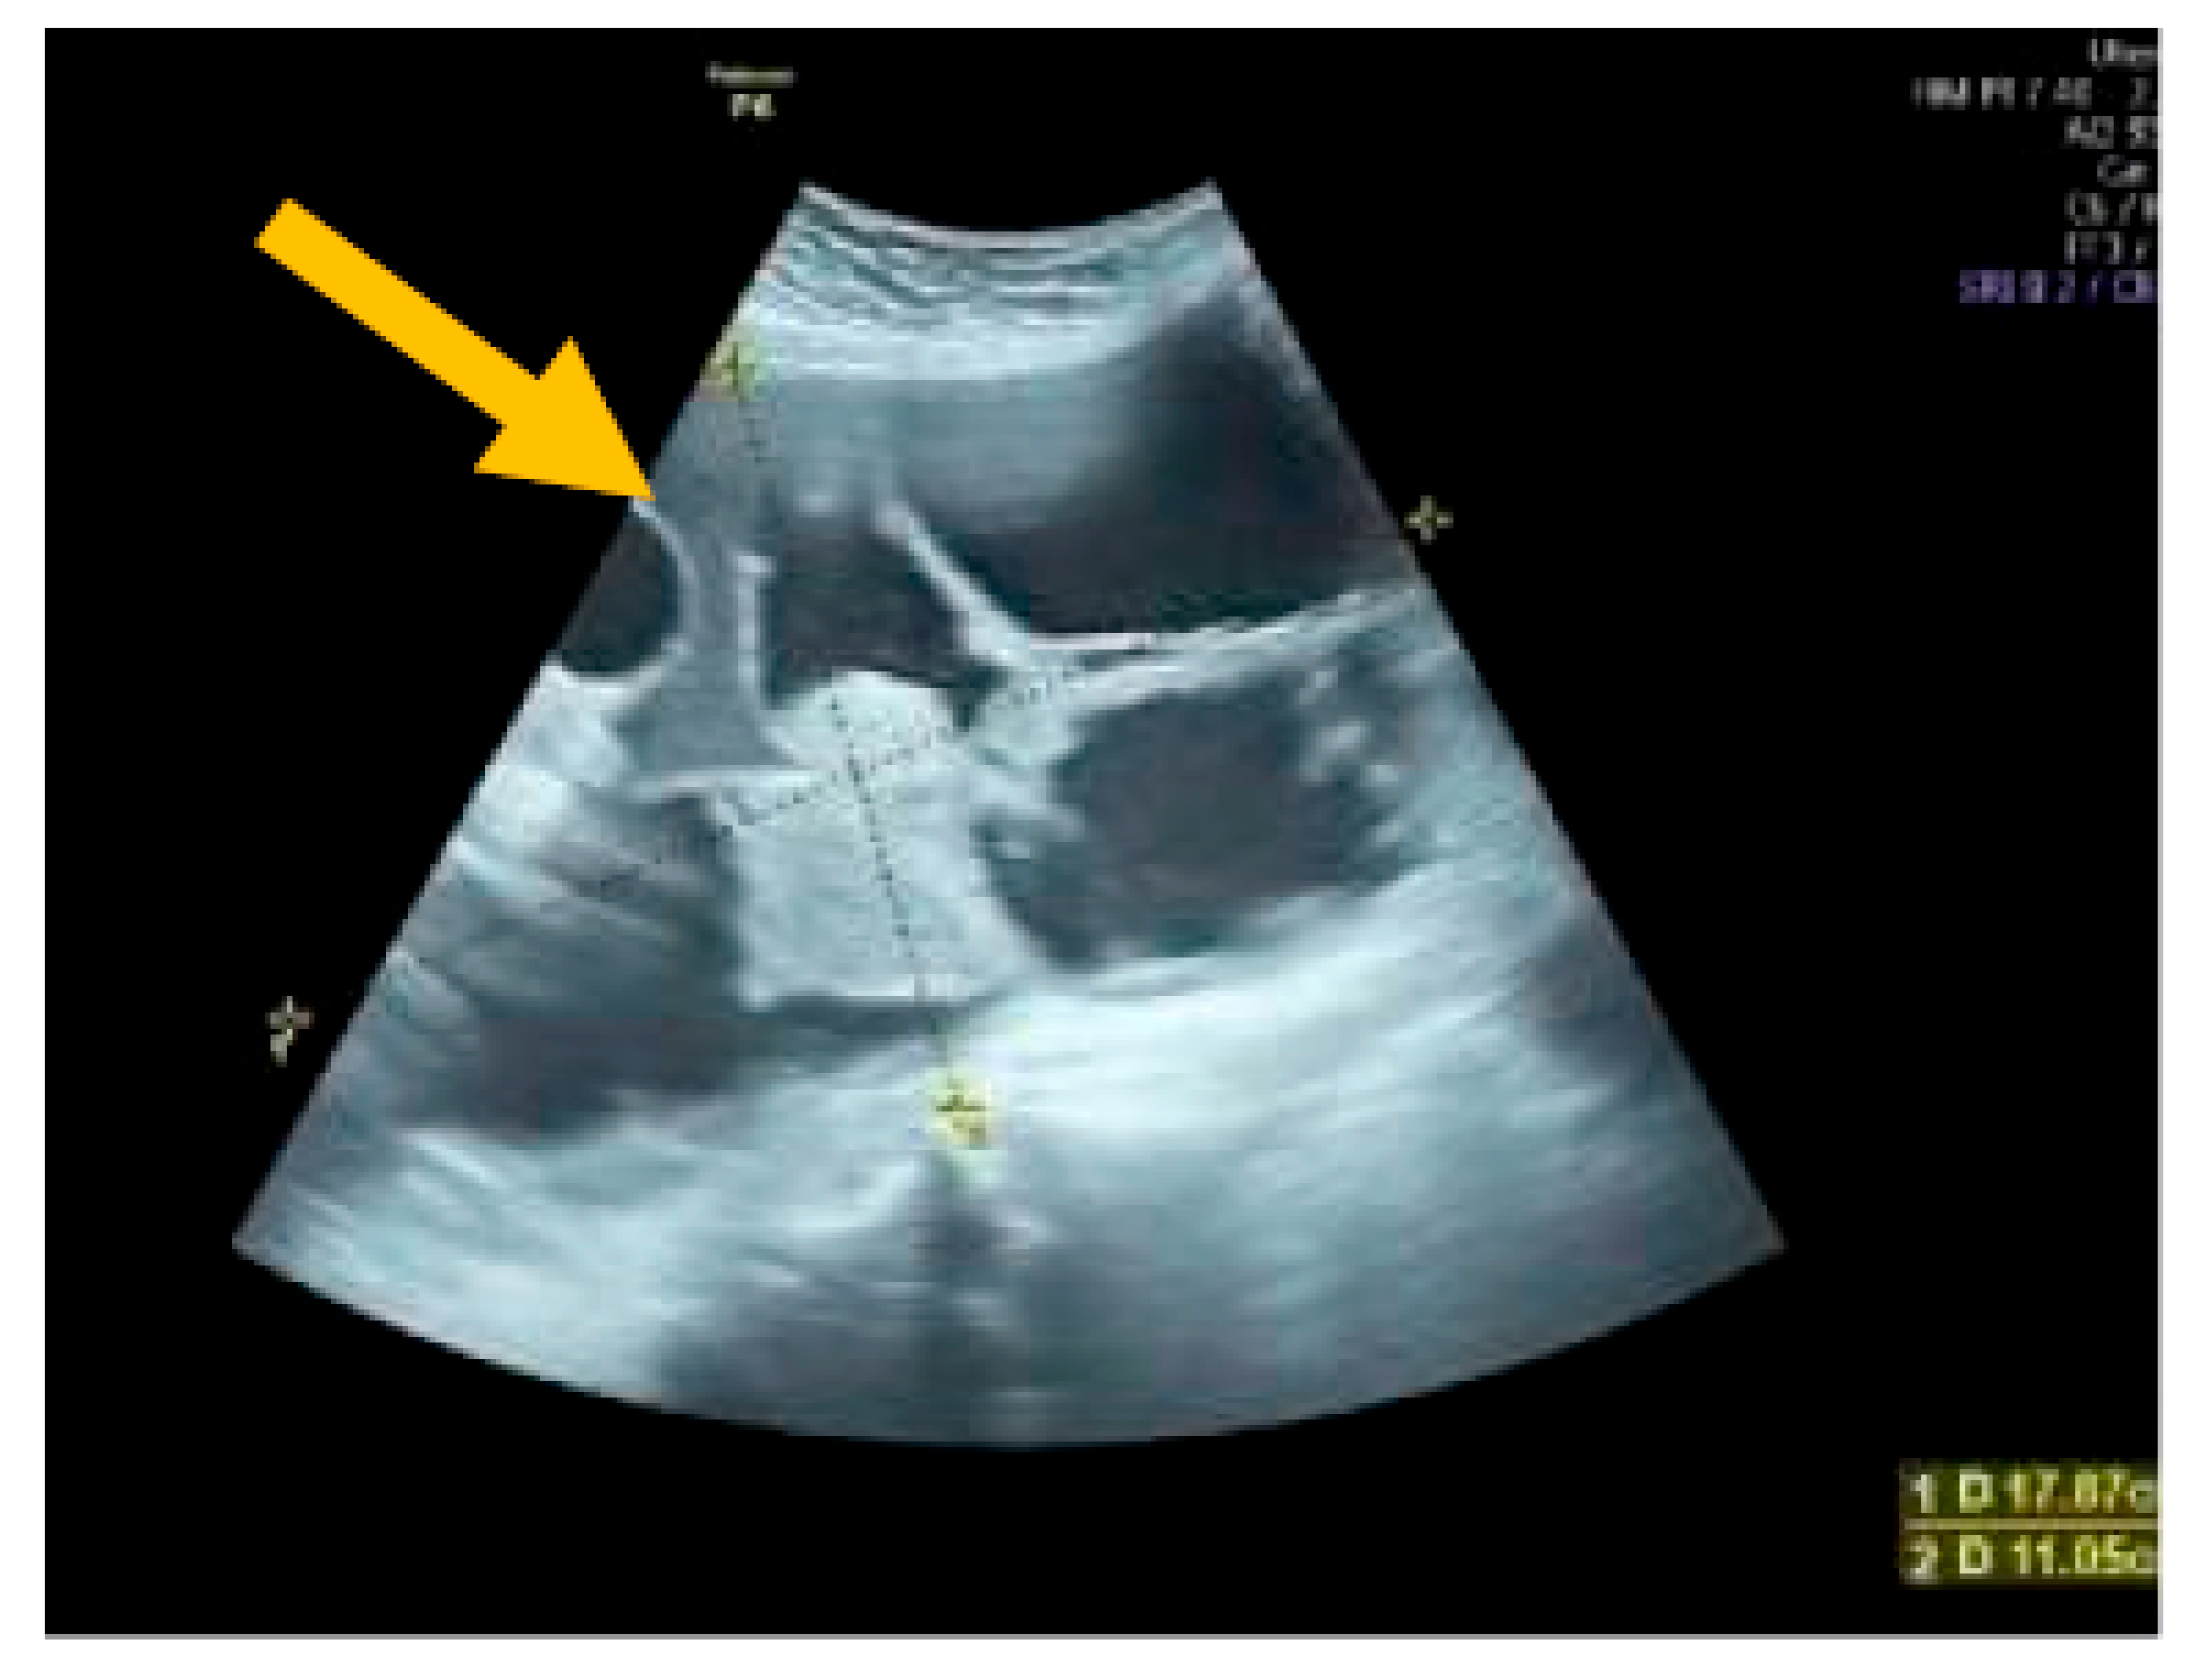

The existence of irregular solid tumors, ascites, at least four papillary structures, an irregular multilocular-solid tumor (diameter at least 10 cm), and very strong blood flow on a color Doppler assessment are malignant indicators, whereas a unilocular cyst, the presence of solid components (max diameter < 7 mm), the presence of an acoustic shadow, a smooth multilocular tumor (max diameter < 10 cm), and the absence of detectable blood flow on the Doppler predispose for the presence of a benign mass [24] (Figure 1, Figure 2 and Figure 3).

Figure 1. Unilocular cyst. (Yellow arrows indicate the presence of a cyst with one locule, no solid components and no papillary projections, while blood flow is absent).